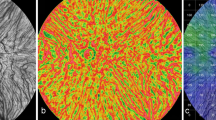

Autocorrelation

In a histogram of the Pearson correlations of all 18 images, the distribution of the Pearson correlation is nonsymmetrical; hence, the statistical median is the measure of preference to quantify the central tendency of the correlation. Fifteen eyes had more than moderate correlation. (Fig. 2a). Thus, the median that we obtained for the 18 Pearson correlations that we computed is 0.9406 (very strong correlation).

Cross correlations

The cross correlation for each image between two masked observers showed moderate to high correlation in 15 cases (Fig. 2b) with the median cross correlation of approximately 0.54.

We also sorted the intra-class correlations and averaged the 9th and 10th correlations to obtain the median correlation measure; hence, the median accuracy of the detection is calculated 0.94.